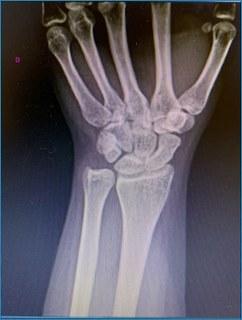

Visualizando a radiografia abaixo, a estrutura da mão que pode estar lesionada após trauma e ser responsável pela fisiopatologia do dedo em botoeira é:

Qual estrutura foi lesionada?

ALigamento anular

BLigamento retinacular oblíquo

CLigamento triangular

DBanda central